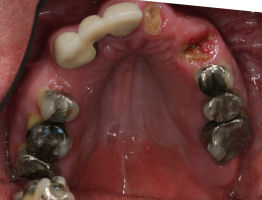

Before/After